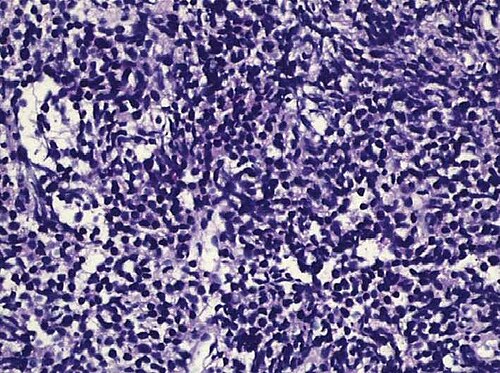

Liver phantom with multiple focal lesions including hemangioma, hepatocellular carcinoma, cyst, and metastasis for...